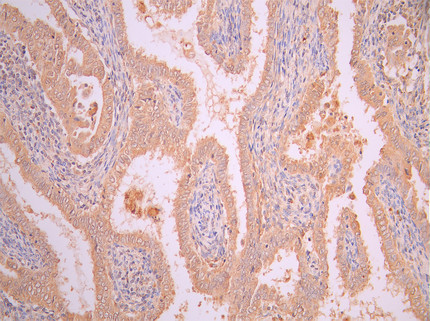

● FAP抗體

FAP Recombinant Monoclonal Antibody; CSB-RA008424MA1HU

FAP Recombinant Monoclonal Antibody; CSB-RA008424MA2HU